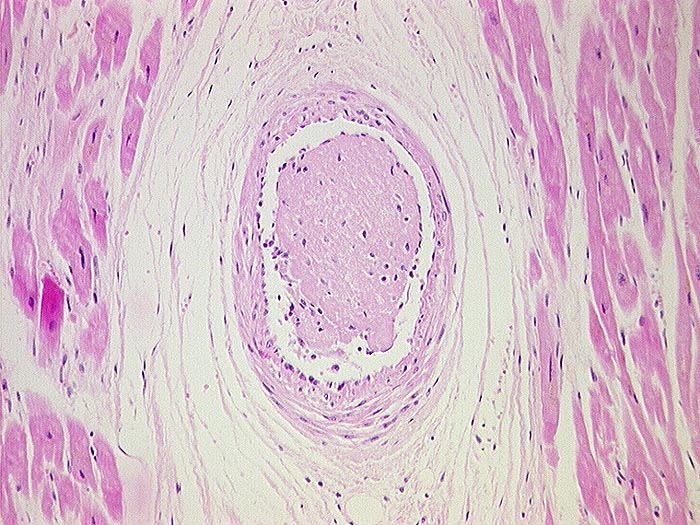

Koronarembolie bei Endocarditis marantica

Arteria coronaris

In einem intramyokardialen arteriellen Gefäss liegt ein frischer Fibrinthrombus, der sich aus der Vegetation (Fibrin!) einer Endocarditis marantica gelöst hat.

non bacterial thrombotic endocarditis

Endocarditis marantica bei Tumorleiden. Todesursache ist ein koronarembolischer Myokardinfarkt.